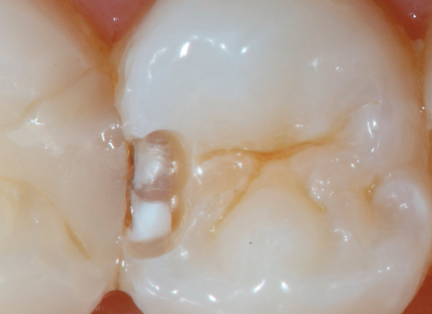

An example of this is the case involving tooth #13, which has two lesions on the mesial. As the CariVu images show, the deeper, more invasive one is toward the buccal and is an established enamel caries lesion that reached the DEJ at a single point. The second one is more to the lingual and is an established enamel caries lesion (Fig. 13). The bitewing X-ray shows a lesion that is apparently of iatrogenic origin (Fig. 14). It did not appear to be near the DEJ. I had not treated this area and continued to observe it since the patient came to me in 2012. With CariVu, I was able to more clearly see the depth of the lesions and decided to restore it. Interestingly, the photo of the open-tooth molar shows that the lesion on the mesial is deepest at the lingual portion of the box (Fig. 15).

Fig. 14 Fig. 15

When using the “occlusal view,” I can actually see the transition from enamel to dentin and where the caries appears to that point. Often, this can be easily missed on a bitewing X-ray, but with a view looking straight down at the tooth, the broader area provides an easier and more evident diagnosis in which I can have confidence.